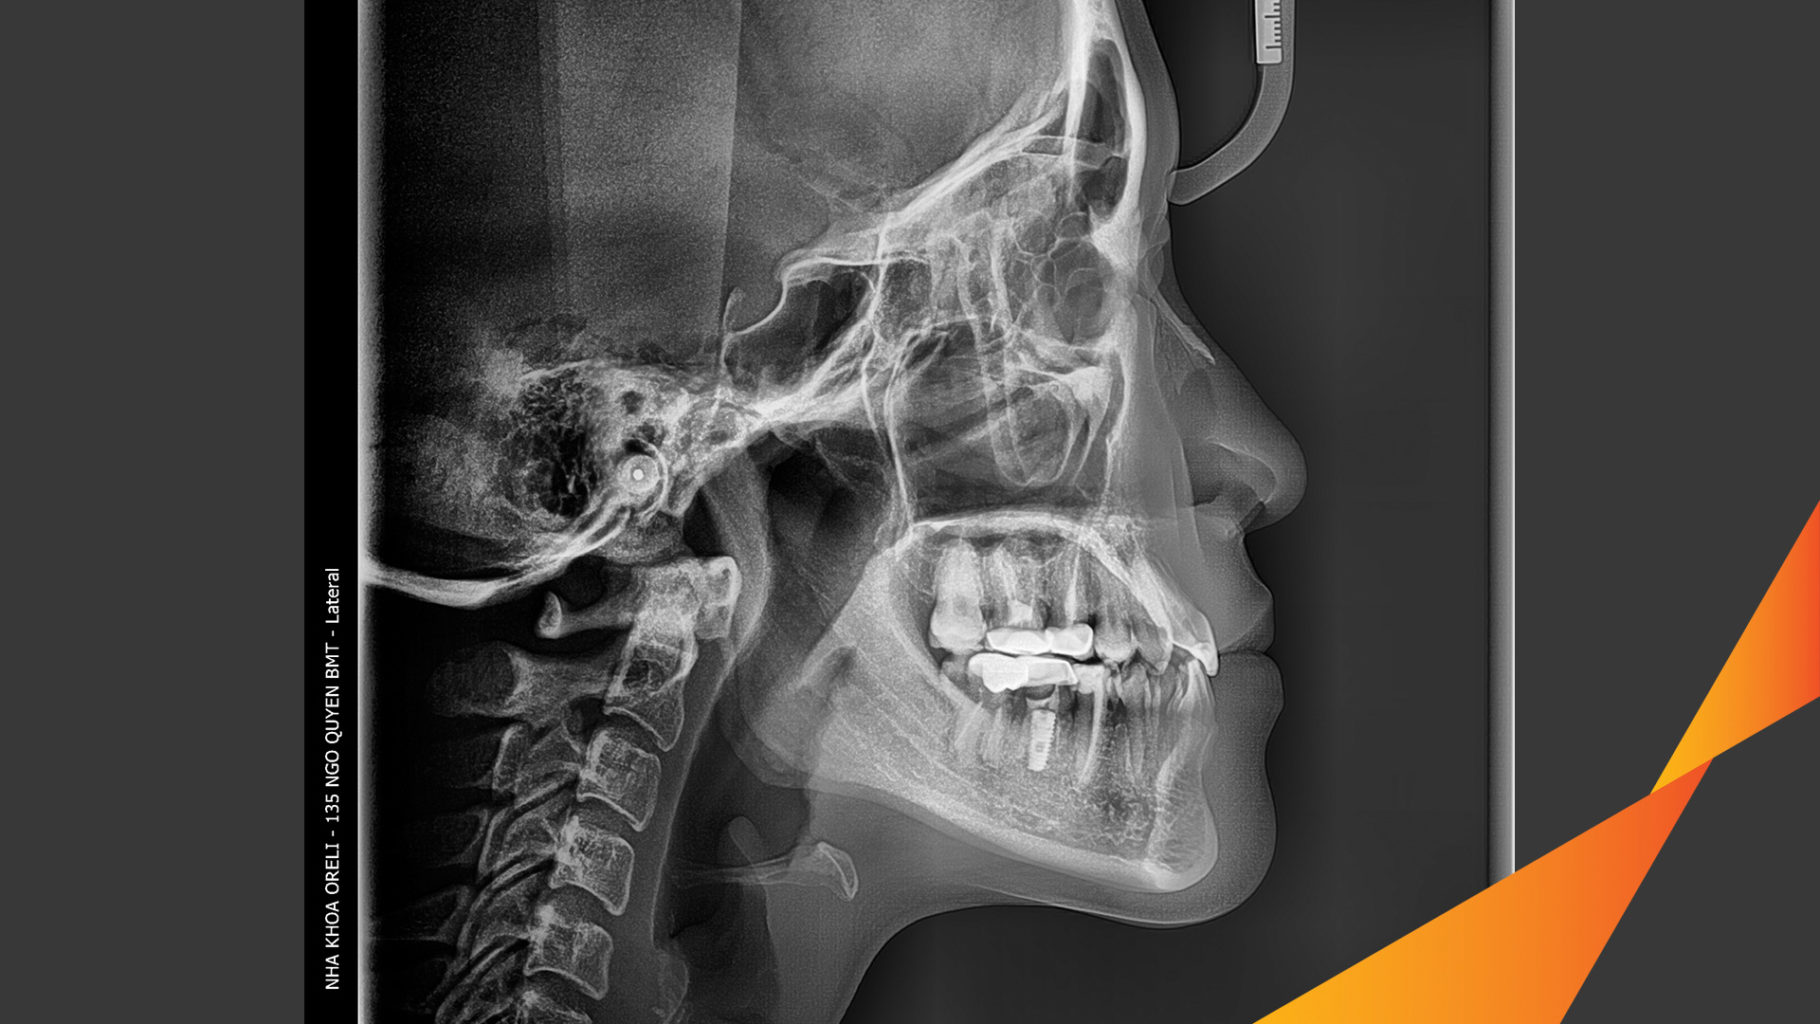

Ca niềng hạng 3 móm di gần răng 78 cho nụ cười đẹp ở Oreli

Ca niềng răng di gần răng 7 8 phục hồi ăn nhai và thẩm mỹ nụ cười. Kết quả thực tế trước và sau điều trị tại Nha khoa Oreli.